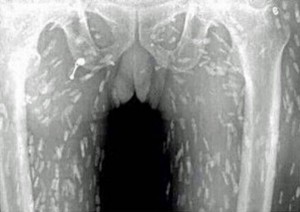

Il mange des sashimis et contracte une horrible infection parasitaire

Fan de sushi, sashimis et autre nourriture asiatique, sachez qu’après avoir vu ces photos, il se peut que vous n’ayez […]

Fan de sushi, sashimis et autre nourriture asiatique, sachez qu’après avoir vu ces photos, il se peut que vous n’ayez […]